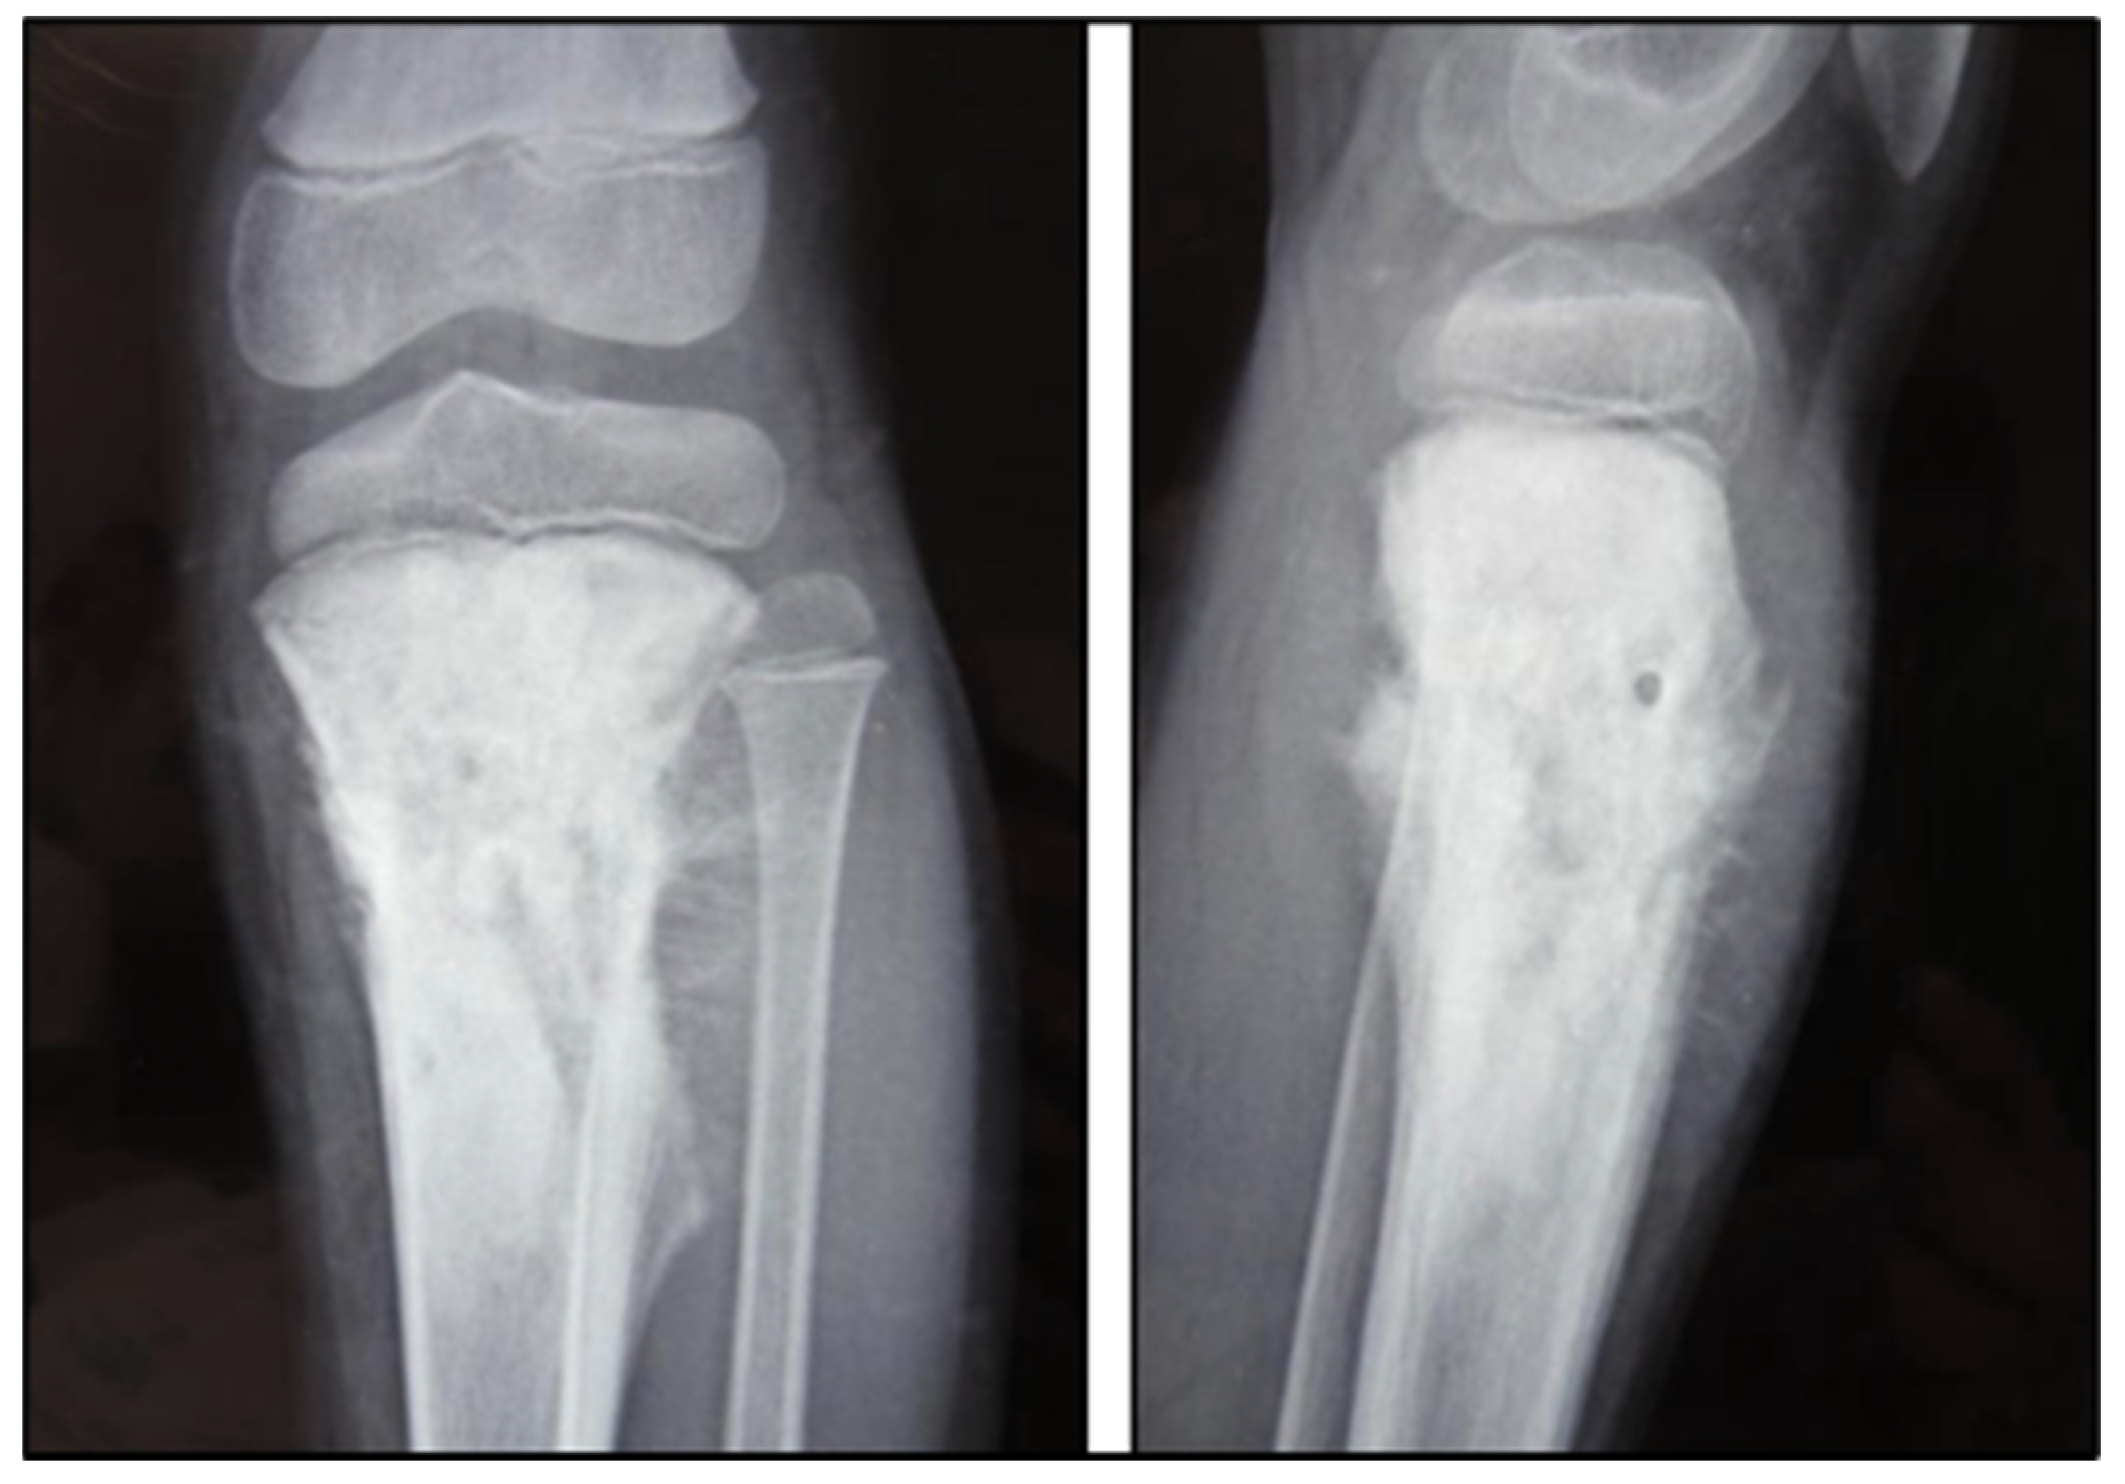

Figure 3. A 9-year-old child’s left knee joint and leg were radiographed in AP and lateral projections. A sclerotic lesion involving the diametaphyseal region of the tibia with a broad zone of transition, osteoid matrix, periosteal elevation (Codman’s Triangle), and the distinctive “Sunburst” type of periosteal reaction is seen on radiographs. There is no discernible intra-articular extension or soft tissue involvement. Radiopaedia.org.

Sarcomatous osteogenesis induces the appearance of linear, coarse, thick “sunray” calcific beams implanted perpendicular to the axis of the bone (Figure 3).

In the pure thickening or osteolytic forms, the semiological criteria are the same, with poor periosteal reactions in the former and intense reactions in the latter.